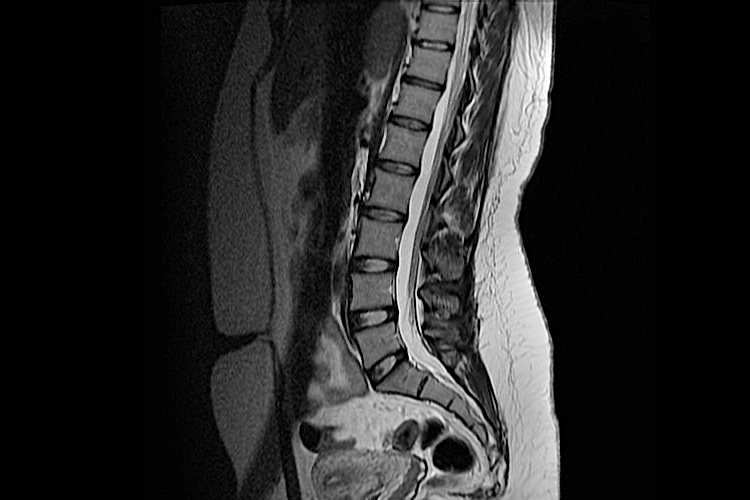

МРТ позвоночника назначается для изучения его важных структур. В ходе обследования врачи исследуют состояние всех костных отделов позвоночного столба, а также его хрящевых тканей, связок и нервов, межпозвонковых суставов и дисков. Исследование позволяет с высокой степенью точности выявить наличие грыж на позвоночнике, определить дегенеративные изменения и зафиксировать воспалительные процессы.

Для всех отделов позвоночного столба предусмотрено отдельное МРТ. Длительность процедур не превышает 20 минут. Исследования отличаются безопасностью, так как проводятся неинвазивно, без лучевой нагрузки.

По завершении этого вида обследования на снимках можно детально рассмотреть:

сужение спинномозгового канала;

дистрофию позвонков;

толщину межпозвоночных дисков;

состояние тканей в изучаемой области.

МРТ поясничного отдела диагностирует такие опасные заболевания, как рассеянный склероз, остеомиелит, остеохондроз, грыжи в области межпозвоночных дисков и воспаления спинного мозга. По итогам обследования можно также точно определить наличие переломов и смещения позвонков.

О том, что показывает МРТ поясничного отдела позвоночника, подробно сообщает врач, выдающий направление на диагностику. Зачастую этот вид исследования назначается при наличии резких болей в районе поясницы, слабости нижних конечностей и защемлении позвоночного нерва.